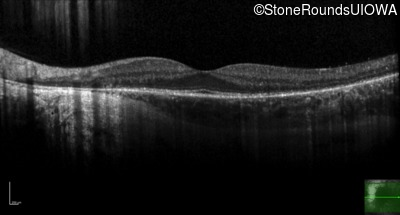

Age at visit: 34 years

This 30 year old man has had some difficulty seeing in dim light for the past few years.